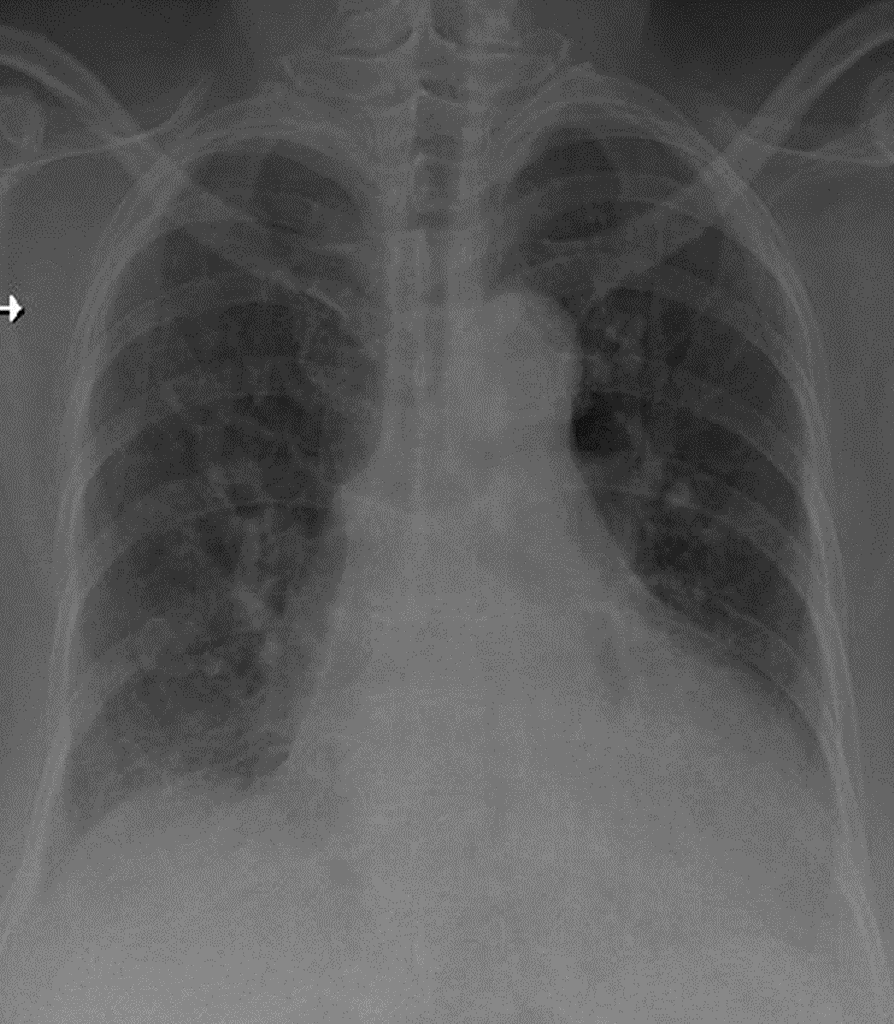

1- Góc carina rộng 2-Bóng tim to -> TD bệnh val tim 3- Cung động mạch chủ đóng vôi